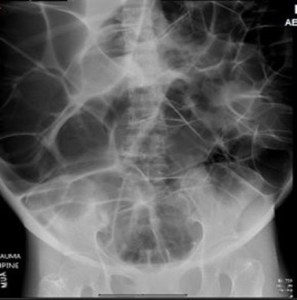

ED abdominal images and workup:

Significant lab results included a non-anion gap metabolic acidosis.

Figure 1. Anteroposterior (AP) abdominal plain film obtained in the ED.

Figure 2. supine cross table abdominal plain film obtained in the ED.